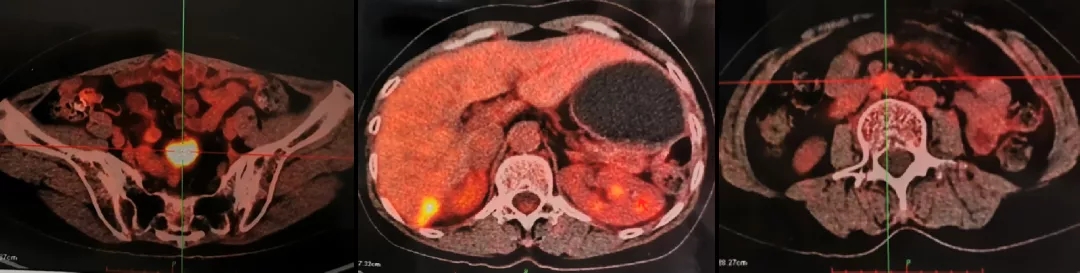

2013.5.10 PET-CT:肝肾隐窝、脾肾间隙、脾门旁、腹膜后可见斑片状、囊实性及结节状影,实质部分FDG代谢增高,考虑转移。

2013.5.10 PET-CT检查结果

PET-CT检查结果

2021.5.8 PET-CT:肝肾隐窝转移灶。2021.5.12复查CA125水平为95.5U/ml。